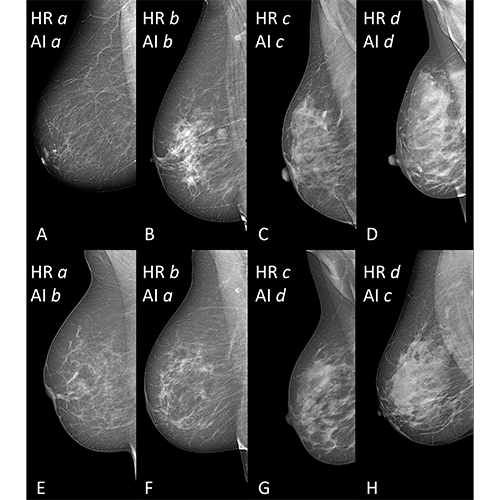

Selection of mammographic mediolateral oblique views of breasts with different breast density from women between 51 and 68 years of age. (A–D) Examples of human readers (HR)-(AI) agreement for category a (68 years), b (66 years), c (51 years), and d (54 years); B shows an example of a breast with a benign mass. (E–H) Examples of HR-AI disagreement; E was classified as a by HR, and as b by AI (67 years); F was classified as b by HR, and as a by AI (68 years); G was classified as c by HR, and as d by AI (55 years); H was classified as d by HR, and as c by AI (52 years). Note - Breast Imaging Reporting and Data System (BI-RADS): category a (almost entirely fatty), category b (scattered fibroglandular), category c (heterogeneously dense), category d (extremely dense).